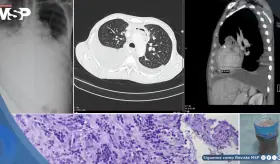

Meses después, desarrolló síntomas gastrointestinales y adenopatías torácicas que inicialmente hicieron sospechar una progresión metastásica, pero las biopsias revelaron granulomas no caseificantes sin células tumorales.

A pesar de mostrar un aumento radiológico del tumor durante la quimioinmunoterapia neoadyuvante, la cirugía reveló una respuesta patológica completa, subrayando la complejidad de la pseudoprogresión.